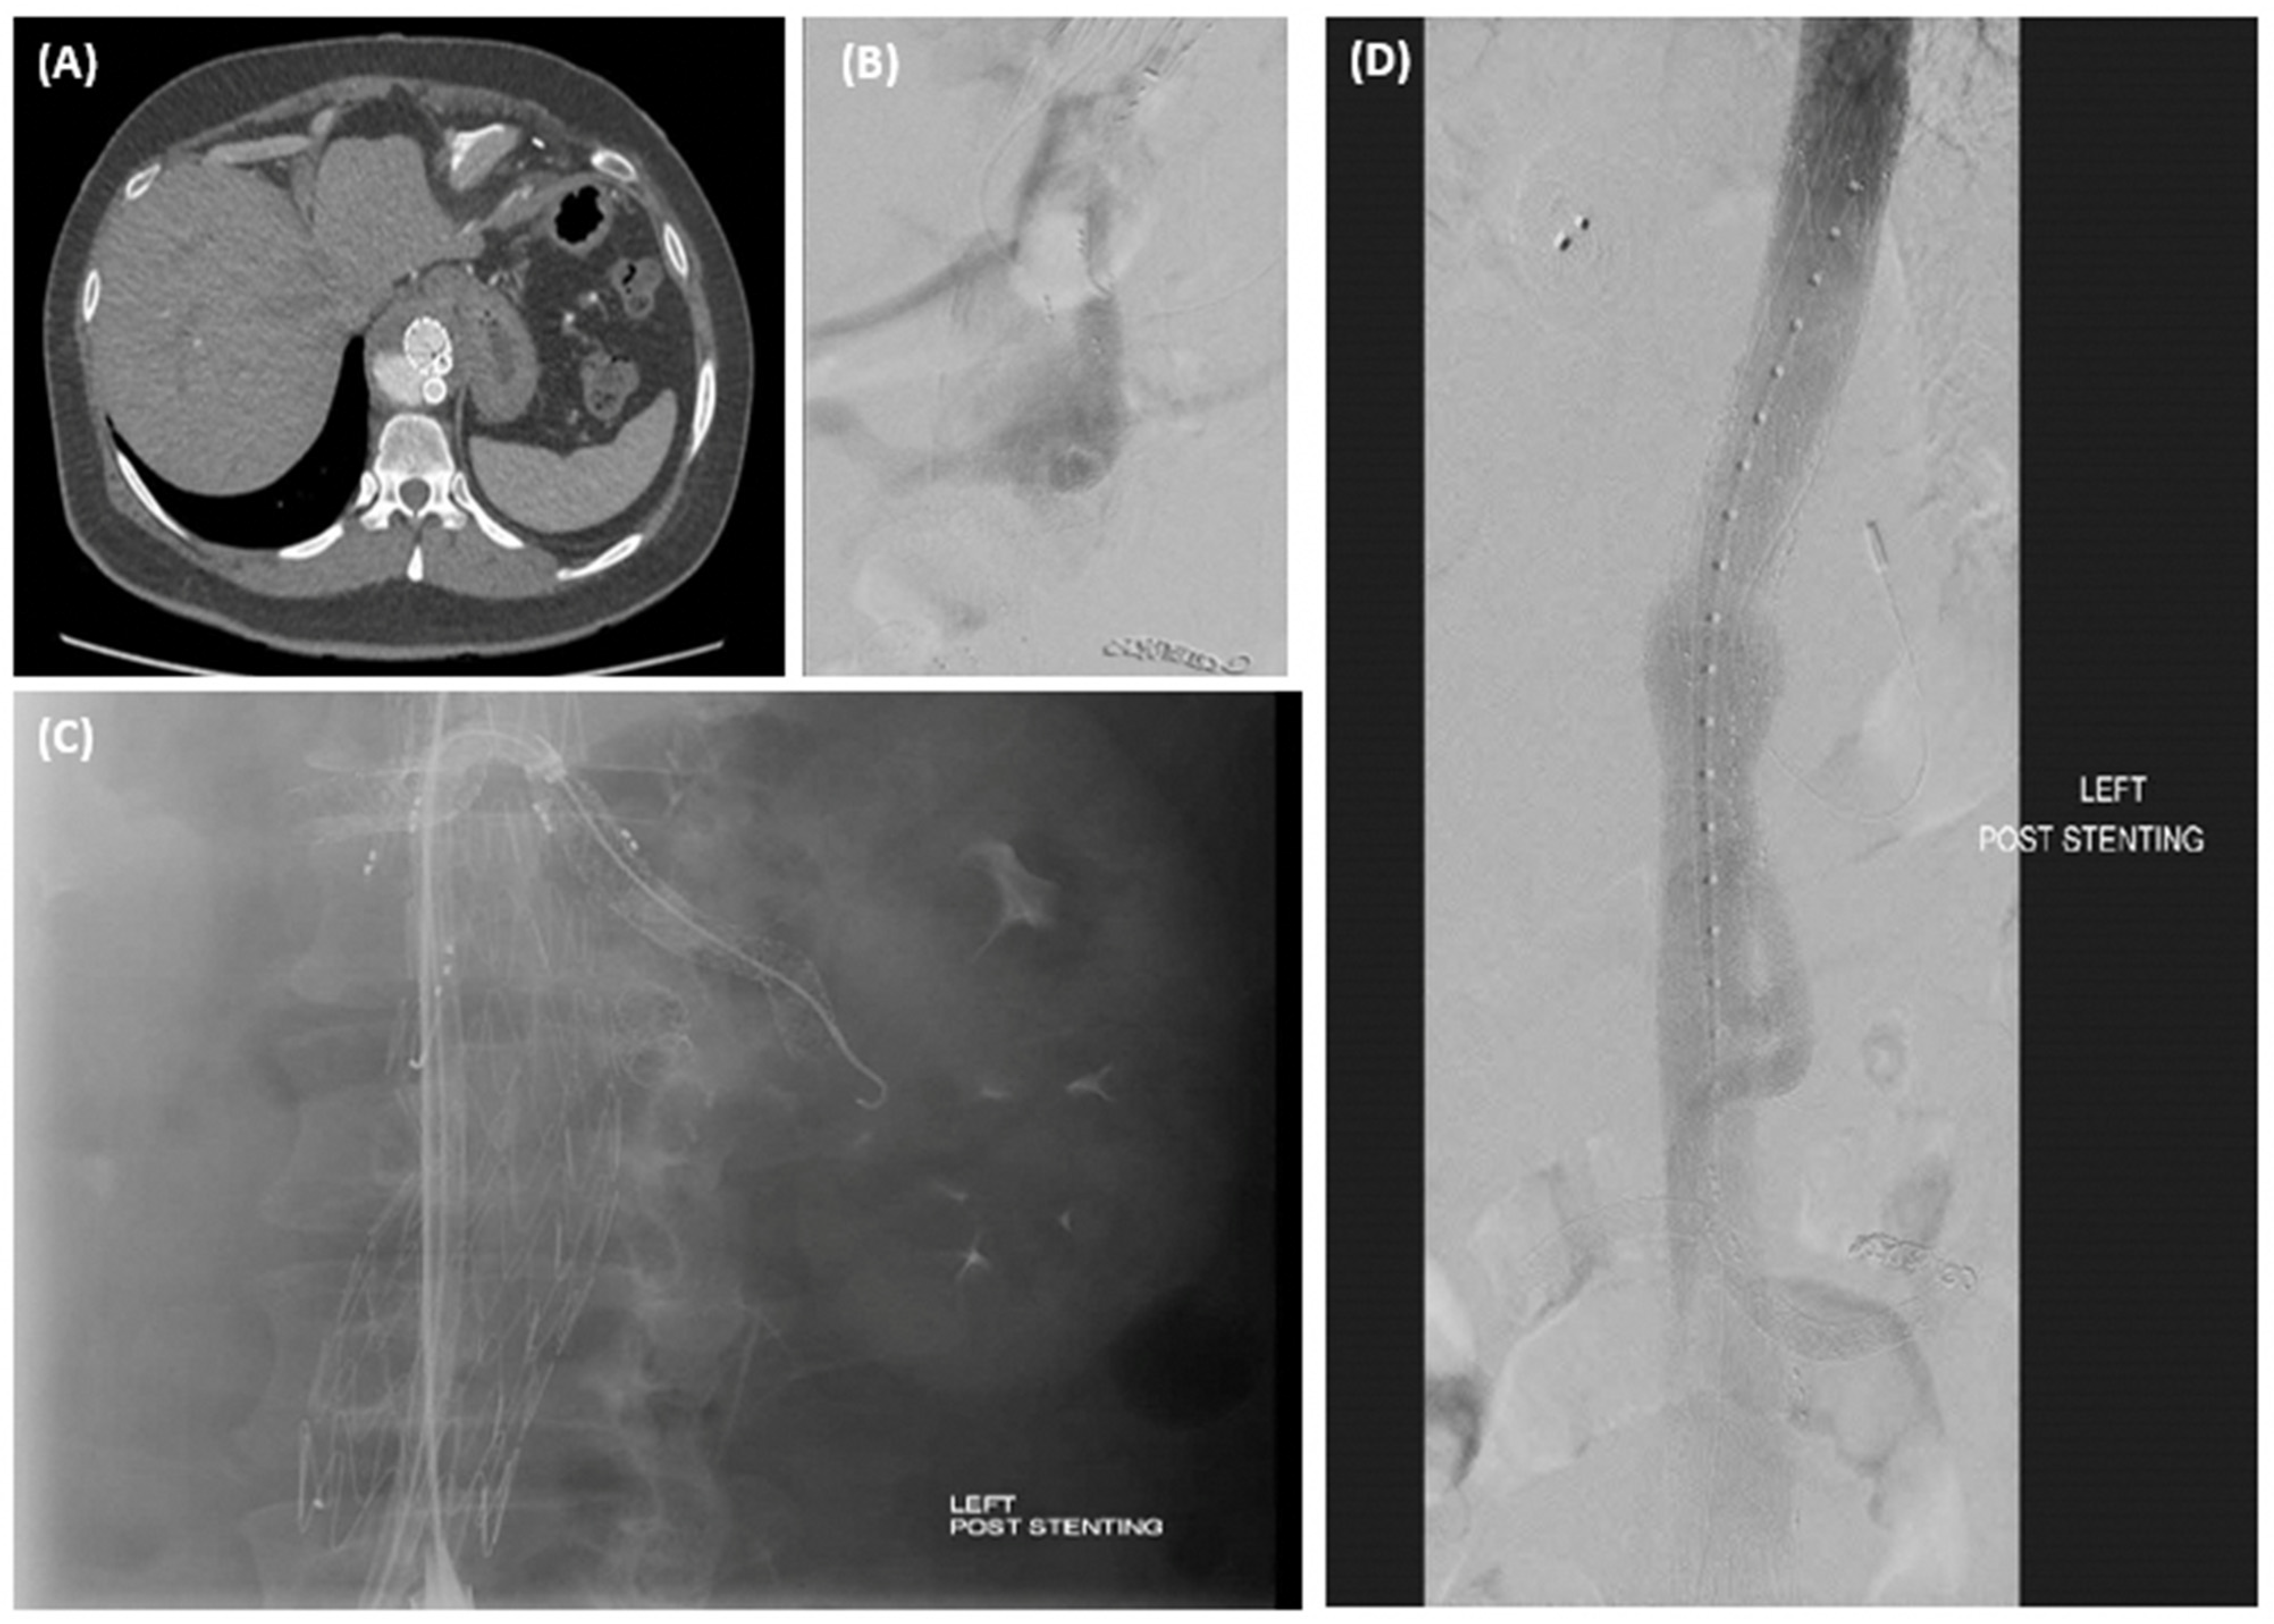

Branch occlusions | All > 1 year incidental on surveillance 4 renal—3 patients, 1 bilateral underwent thrombolysis, 2 unilateral—treated conservatively |

Aortic limb occlusion | 2 iliac limbs, required thrombolysis and relining |